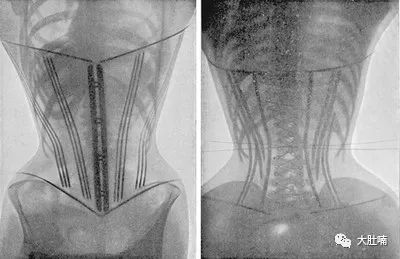

X光片的确凿证据(穿着束胸衣女性)

这么说吧

女性的盆底本由非常强韧的韧带牵拉

以保持脏器处于正确姿态

但束胸衣却能将其压下降约0.9厘米

子宫正常的位置变了

就可能引发子宫脱垂等症